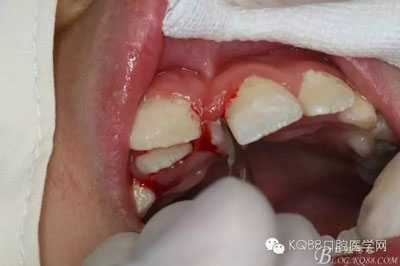

圖1.術(shù)前的患者口內(nèi)照片:11與12完全唇腭向重疊,11與21之間有3mm間隙